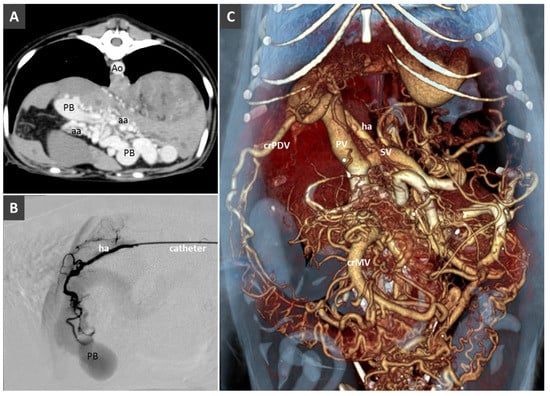

Congenital Portosystemic Shunt

3.8. Porto-Portal Collaterals or Cavernous Transformation of the Portal Vein